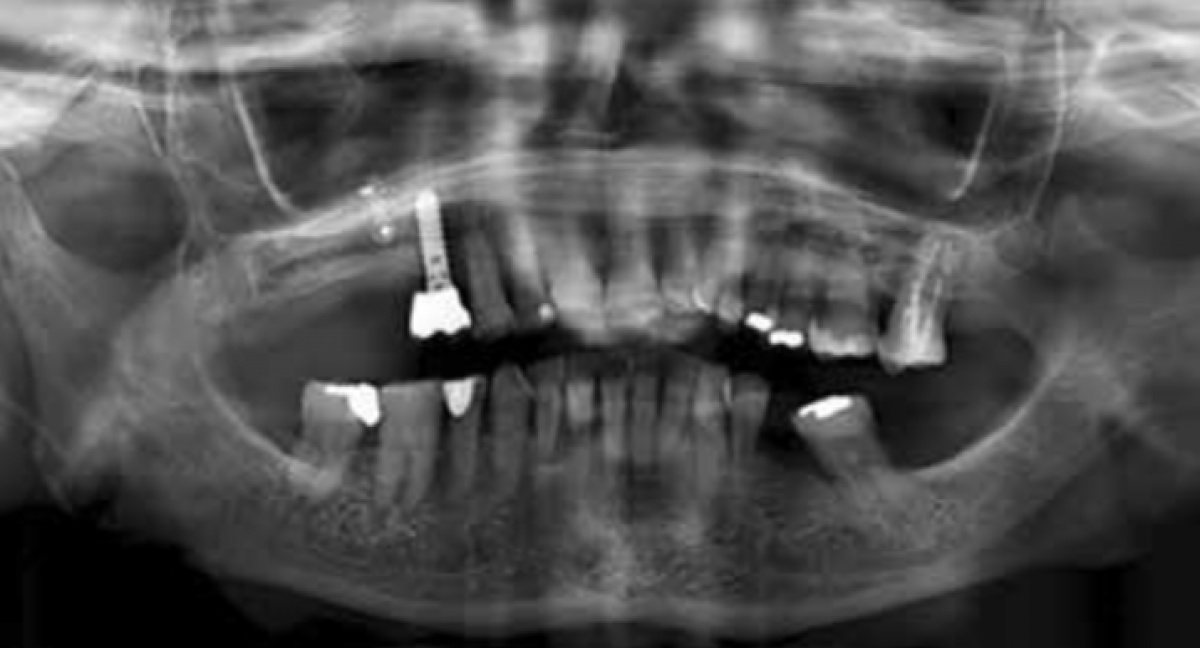

18-year-old patient with multiple carious lesions located in the first quadrant.

After the radiographic examination, the surgical field was isolated with a rubber dam and the carious lesions were removed with diamond burs with decreasing grain size and multi-blade tungsten carbide burs.